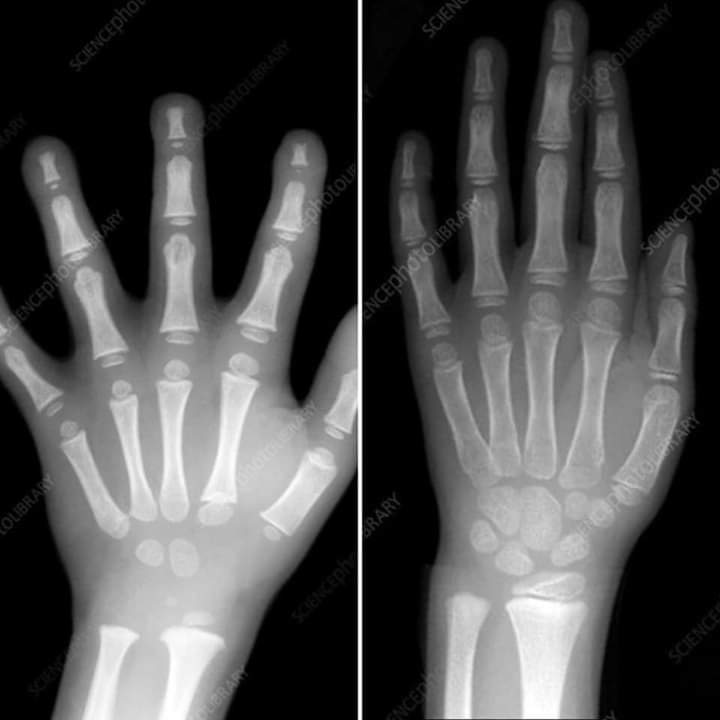

En la radiografía de la imagen superior podemos observar la mano de un niño de 5 años (izquierda), y la mano de un niño de 7 años (derecha). A simple vista, se puede observar las enormes diferencias en el desarrollo óseo. Si los huesos no están desarrollados el control motor de la musculatura de la mano se vuelve imprecisa.

El sistema locomotor y nervioso son los responsables del movimiento. Cuando estos sistemas no están maduros, agarrar un lápiz y pretender realizar una grafía adecuada se vuelve arduo y tedioso.

Adquiere un patrón motor con unas condiciones biológicas diferentes a las que tendrá en el futuro, consiguiente, el niño deberá de volver a aprender a escribir con sus nuevas dimensiones biológicas. Esta es la razón por la que suele aparecer un periodo de empeoramiento. El niño no empeora. Es solo que su esquema corporal se ha modificado, y por lo tanto, el niño tiene que readaptar la escritura a sus nuevas condiciones.